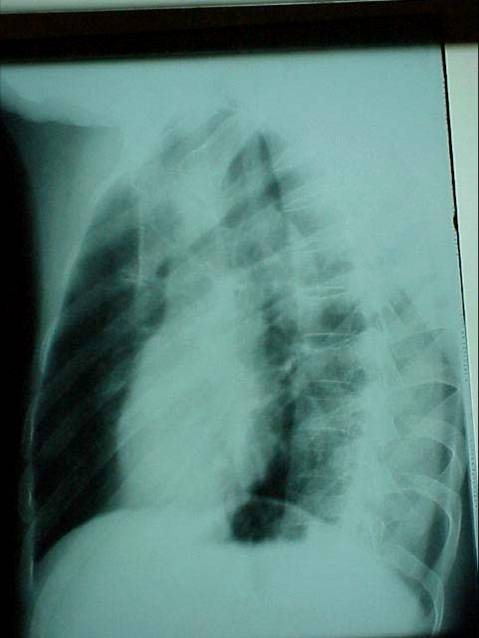

X射线

右前斜位(图)

右前斜位